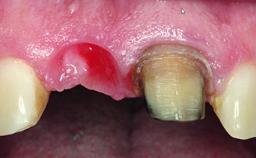

Replacement of a Failing Upper Left Central Incisor: Immediate Placement of an RC Bone Level Implant and Provisionalization

A healthy 23-year-old female patient was referred for a consultation on replacing tooth 21 with an implant-supported restoration. The patient had recently moved to the area and reported a history of endodontic and periodontal treatment for tooth 21. The tooth had been deemed non-restorable by her previous periodontist but since she was going to be moving, he recommended consulting to a dentist in her new city to continue her treatment. A review of her medical history yielded no significant findings and no known drug allergies. The analysis of her smile revealed a medium to high symmetrical smile line and a slightly discolored tooth 21.

Soft Tissue Anatomy Intact Defective

Soft Tissue Contour and Volume Ideal